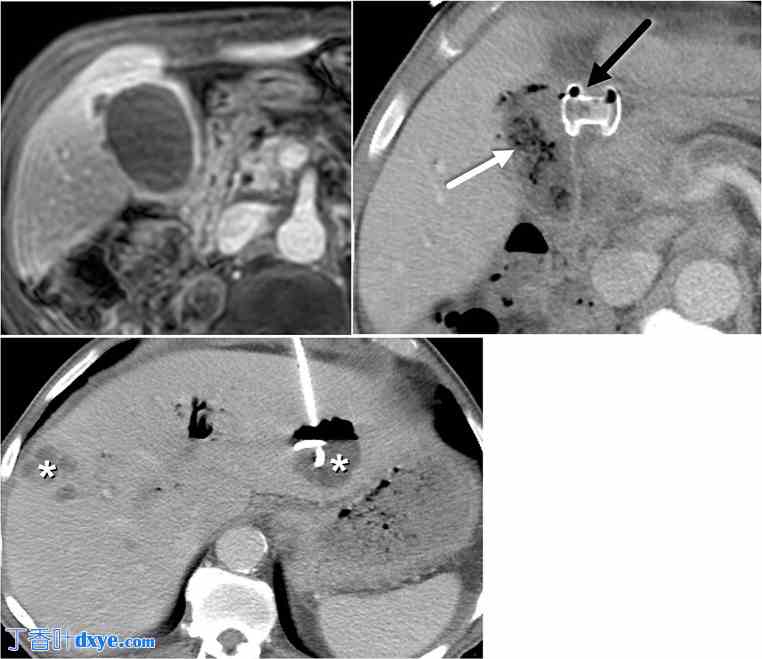

随着 LAMS 在内镜胆囊引流中的应用越来越广泛,并得到 FDA 的批准,放射科医生应注意其各自的相关风险、禁忌症和并发症。一项包括 393 名使用 LAMS 进行 EUS-GBD 的患者的荟萃分析显示,总体不良事件发生率为 12.7%,包括出血、支架移位、支架阻塞、复发性胆囊炎或胆管炎、胆漏、穿孔(十二指肠或胆囊)和死亡(图 4)。EUS-GBD 的禁忌症之一是坏疽性或穿孔性胆囊炎,因为泄漏风险增加,并且由于胆囊壁易碎而形成脓肿(图 5)。对于未来可能接受肝移植的内镜胆囊引流术候选人来说,一个重要的考虑因素是,ET-GBD 是该群体的首选,因为它可以保留胆囊的天然胆道解剖结构和结构完整性。由于这些原因,建议考虑进行内镜胆囊引流术的患者接受多学科评估。

图 4。

4.jpg

73 岁男性,患有胰腺癌和急性胆囊炎。A. 轴向 CT 图像显示 LAMS-胆囊胃造口术(粗白箭头),旨在缓解急性胆囊炎。Axios 明显从胆囊中移位或移位,在肝周间隙中观察到口服造影剂(粗黑箭头),以及气液平面(灰色箭头),表明存在气腹和腹水。观察到 LAMS 远端部分的腔外造影剂泄漏(细黑箭头)。在 CBD 中观察到含有造影剂和少量空气的胆道支架(细白箭头)。 B. 轴向 CT 图像显示盆腔腹水中的液液平面表明存在外渗的口服造影剂与液体混合(白色星号)

图 5。

5.jpg

72 岁女性,患有胰腺颈癌和急性胆囊炎。A. 造影后轴向 LAVA MRI 显示胆囊壁不规则,局部外翻,表明胆囊壁穿孔(白色箭头)与坏疽性胆囊炎有关,这是内镜胆囊引流的禁忌症,但前瞻性地没有发现。B. 随后进行了 LAMS 胆囊胃造口术(黑色箭头)。注意到部分减压胆囊中预期有空气(白色箭头)。 C. 患者出现多个肝脓肿(白色星号),需要经皮引流,最终死于脓毒症